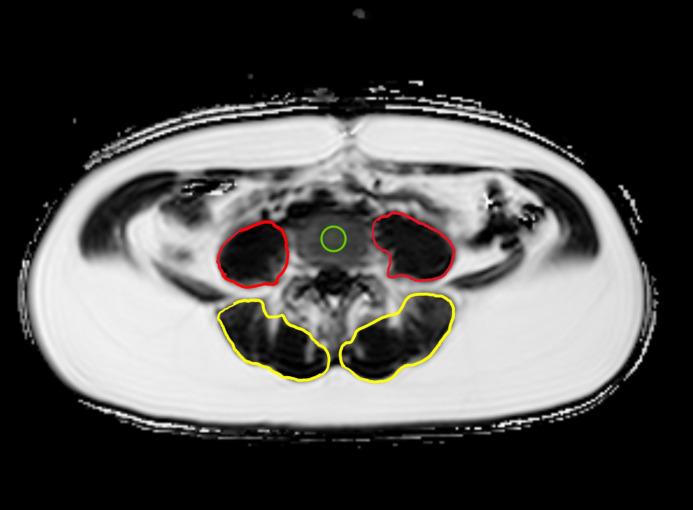

A total of 37 women (mean age 36.3 ± 3.8 years) who were 6 to 15 months postpartum with (n=19) and without (n=18) a history of GDM underwent whole-body 3T MRI, including a chemical shift encoding-based water-fat separation. The PDFF maps were calculated for the vertebral bodies and PSM. The cross-sectional area (CSA) of PSM was obtained. Associations between a history of GDM and PDFF were assessed using multivariable linear and logistic regression models.

共有 37 名产后 6-15 个月的妇女(平均年龄 36.3±3.8 岁)参与了本研究,其中 19 名患有 GDM(GDM 组),18 名无 GDM(对照组)。所有参与者均接受了全身 3T MRI 检查,包括基于化学位移编码的水脂分离。计算椎体和 PSM 的 PDFF 图。获取 PSM 的横截面积(CSA)。使用多变量线性和逻辑回归模型评估 GDM 病史与 PDFF 之间的关系。